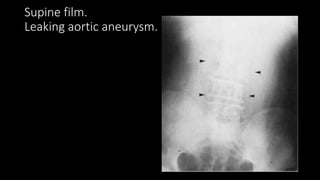

Supine film.

Leaking aortic aneurysm.

Plain film

• Central soft tissue mass which may obscure psoas

outline on the left

• Frequently curvilinear calcification

• Obscured renal outline